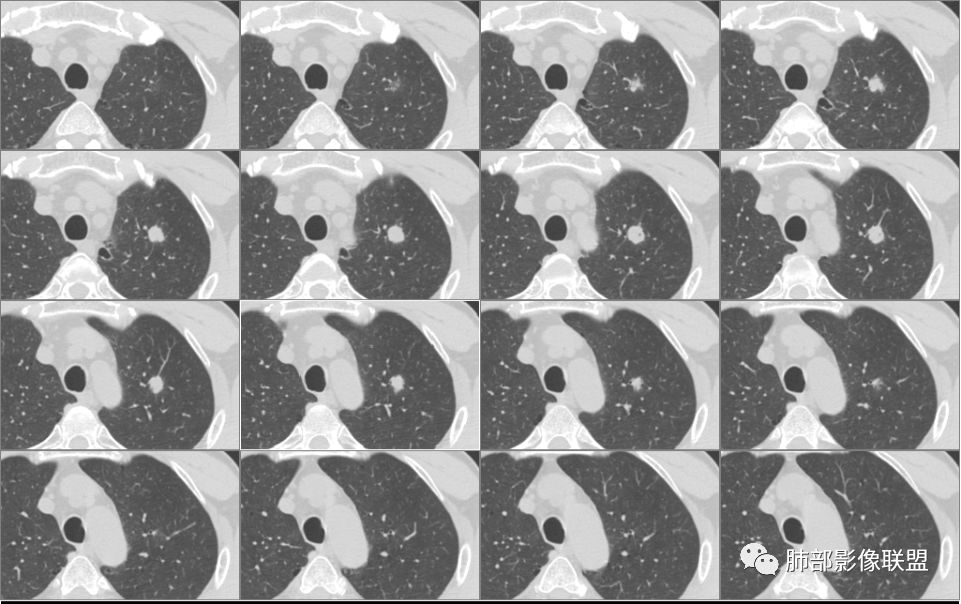

南大分析病例2

南边:

支气管截断。

支气管在门口堵塞恶性居多,结核有时也有。

空泡

分叶

血管纠集

毛刺

总体分析,支持恶性。

病例2病理结果

病例小结

应当说两例患者影像学表现都具有比较明显恶性征象,中老年男性患者,均都没有呼吸系统临床症状。

病例1为胸膜下实性小结节,血管脐凹样出入,可见支气管阻塞。病灶膨隆,部分边缘平直,周围晕征不明显,未见分叶,但可见毛刺及胸膜牵拉,增强后明显强化,老年男性,怀疑新生物尤其是腺癌是有理由的。

病例2肉瘤样癌的病理意见有些出乎预料,也充分说明病变及影像表现的复杂性。病灶小结节支气管截断、空泡、分叶、短毛刺、血管集束征等似乎均符合肺癌的影像特性。肺鳞癌及肉瘤样癌往往范围较小就可以出现坏死,但如果结节太小则很少能够在影像上观察到坏死区或空洞,没有增强扫描图像更是如此。